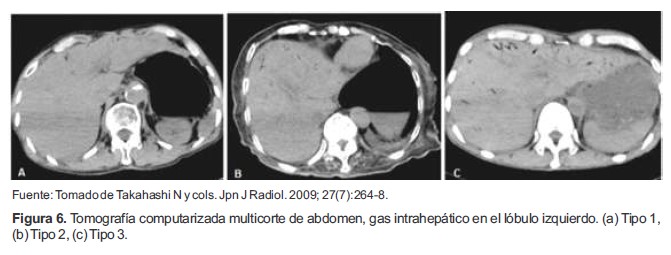

E. Gas intrahepático

La presencia de Gas Intrahepático (GIH), es un hallazgo frecuente en la TC postmortem en casos de muerte no t raumática (55-57) . Por ello, se han realizado investigaciones sobre su detección por TC, para posteriormente confirmar mediante la autopsia convencional. En uno de los reportes, se evaluó la ubicación y ocurrencia de GIH, mediante imágenes por TC multicorte (TCM) en 208 personas fallecidas no traumáticamente (56). La ubicación de GIH fue clasificado en una escala de 0 a 3, siendo 0 la no aparición de ningún gas; 1, gas sólo en el lóbulo izquierdo (Figura 6a); 2, gas en el lóbulo izquierdo y el segmento anterior del lóbulo derecho (Figura 6b); y 3, gas en el lóbulo izquierdo con los segmentos anterior y posterior del lóbulo derecho (Figura 6c), encontrándose que la mayoría de los casos poseían este hallazgo en el tipo 3 de la escala y que esto se correlacionaba con la aparición de distensión intestinal, y el periodo transcurrido entre el paro cardiorespiratorio y el posterior examen y la autopsia.

Figura 6. Tomografía computarizada multicorte de abdomen, gas intrahepático en el lóbulo izquierdo. (a) Tipo 1, (b) Tipo 2, (c) Tipo 3.